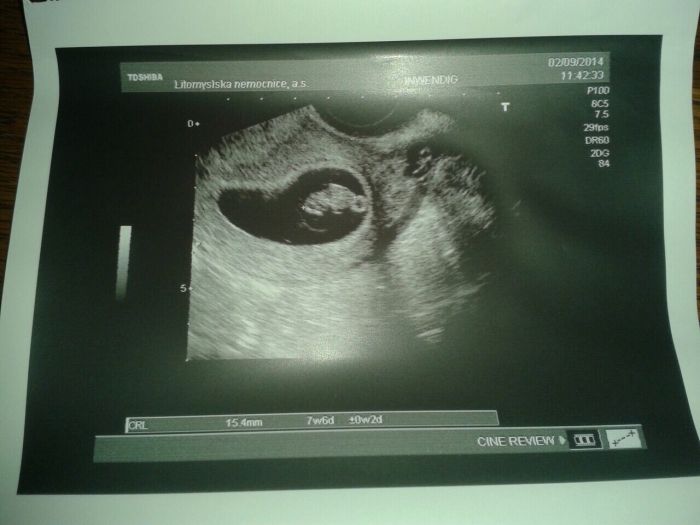

Krásné fotečky máte!! Tak pro úplnost i moje z 8tt.